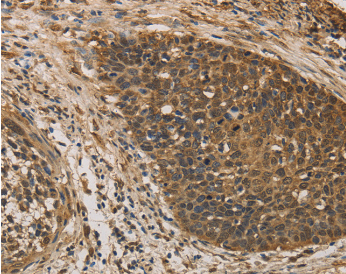

| Immunohistochemistry of Human colon cancer using DACH1 Polyclonal Antibody at dilution of 1:50 |